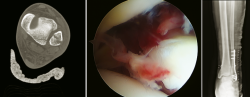

Figura 8. Fractura tobillo SER III. Asistencia artroscópica para valoración de sindesmosis.

- Traumatología de pie y tobillo: fracturas complejas de tobillo, calcáneo, astrágalo y mediopié. Reducción abierta y osteosíntesis con asistencia artroscópica (Figura 8).